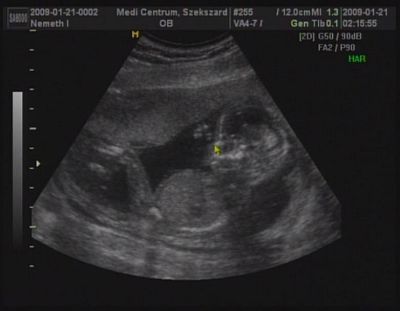

Amúgy uh közben mondta még a dokim, mintha csak úgy magának mormogná, hogy zárt mellkas, meg zárt gerinc, ilyeneket, úgyhogy azzal kapcsolatban már ott megnyugodtam.